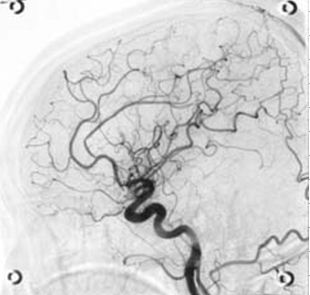

血管撮影装置(1台)

【脳血管造影像】

血管内にカテーテルという細い管を挿入し、その管から造影剤を注入して撮影することで、血管の形状を詳細に観察できます。また、血管の診断だけでなく、治療(IVR)も行うことが可能です。